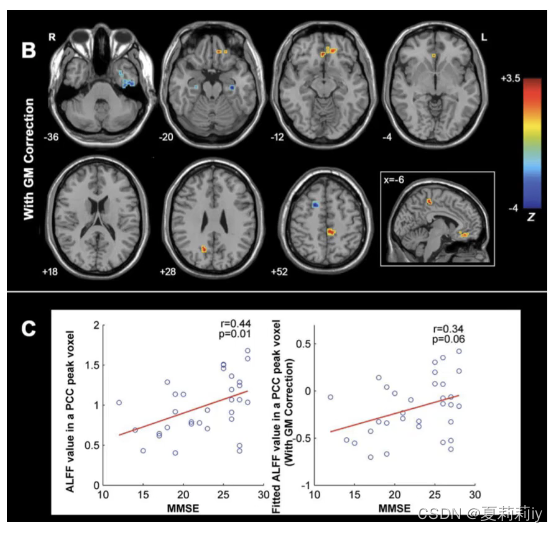

③生成的结果示例

③上图中Covariate Images添加的灰质密度图像,Covariate Images为图像协变量

⑤上图中Text Covariates添加了头动,Text Covariates是文本协变量

②可以直接做ANOVA,也可以在做的时候先做多重比较矫正。看结果可以用Z值